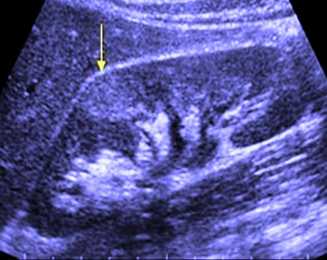

Ультразвуковая диагностика

Использование УЗИ у лиц с ЭП затруднена рядом факторов: большинство пациентов страдают ожирением, многие имеют вздутие живота, из-за чего бывает трудно дифференцировать газ из кишечника с газом в некротизированных почках. Несмотря на все трудности диагностики, ЭП может быть заподозрен у пациентов со следующими находками:

- увеличенные в размерах почки;

- высокоамплитудные эхо-сигналы в почечном синусе и/или почечной паренхиме, связанные с «грязным» затемнением;

- почка вообще может и не визуализироваться из-за деструкции и замещении газом, следует дифференцировать с кишечными газами.

В целом ультразвуковая диагностика с вероятностью 50 % может дать неправильные диагнозы у пациентов с 1 и 2 классами заболевания.

Рисунок 3 | УЗИ левой почки пациентки 50 лет с СД и ЭП. Увеличенная левая почка с нарушенной кортикомедуллярной дифференцировкой и линейными воздушными тенями в нижнем сегменте.